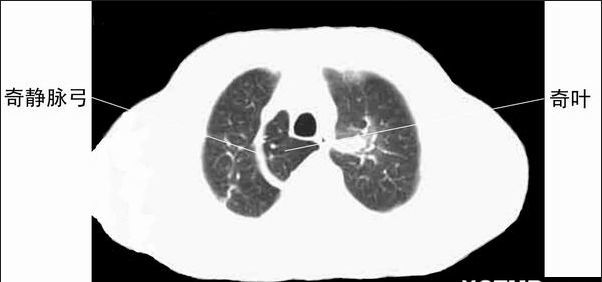

奇叶蕨

奇叶